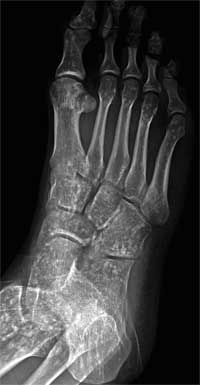

A 21-year-old man presented for evaluation after he sprained his right ankle while hiking. Radiographs of the ankle showed no fractures but revealed diffuse sclerotic lesions in most of the visualized bones.

These hyperostotic areas of bone represent osteopoikilosis, a benign, autosomal dominant condition that occurs in about 1 in 50,000 persons.1 The pelvic, carpal, and tarsal bones or the epiphyseal ends of long bones are most often affected.2 Almost all affected persons have metacarpal lesions.1,3 The condition is usually diagnosed incidentally, as in this case.